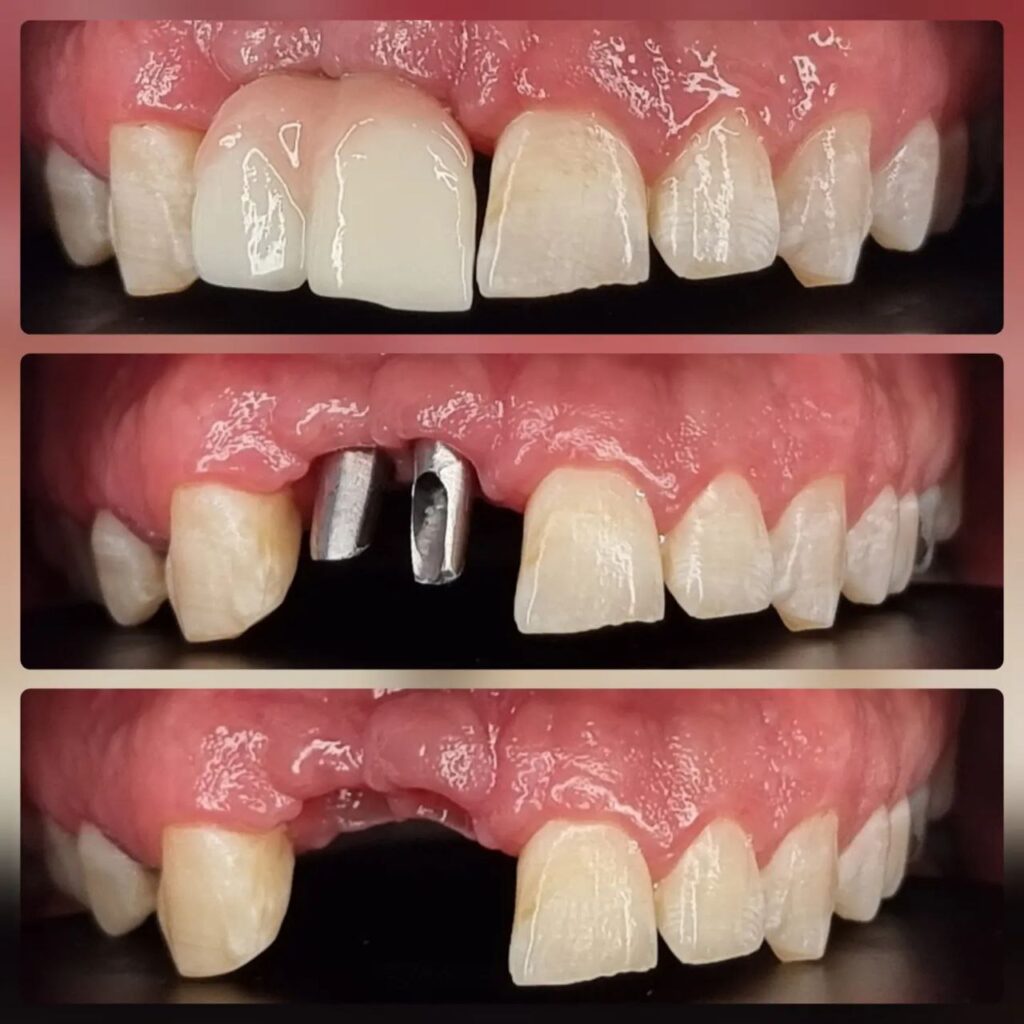

کاشت ایمپلنت دندان

اطمینان حاصل کردن از اینکه دندانهایتان به نحوی زیبا و طبیعی جایگزین شدهاند، از اهمیت بسیاری برخوردار است. ایمپلنت دندان به عنوان یک روش درمانی دائمی در دندانپزشکی شناخته میشود که حاصل آن، یک دندان زیبا و طبیعی در دهان شما خواهد بود.

هرچند که این روش درمانی هزینهی بیشتری نسبت به روشهای دیگر دارد، اما ارزش زیبایی که ایجاد میکند، قابل انکار نیست. ایمپلنتها به قدری شبیه به دندانهای طبیعی هستند که به سختی میتوان آنها را از دیگر دندانها تشخیص داد.